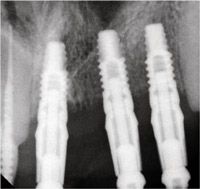

FIGS. 1-4 Clinical view of maxillary arch showing missing teeth (Fig. 1). Axial view showing planned implants in area 8, 9, 10, 12 (Fig. 2). Cross-sectional view showing buccal and lingual bone for implant placement (Fig. 3). Periapical view showing spacing of implants post placement (Fig. 4).

A periapical radiograph confirms the implant placement and spacing as per the plan from the CBCT (Fig. 4). The final prosthesis shows the esthetics that can be obtained through correct planning with a CBCT (Fig. 5). Unless the spacing between implants is correct, the soft tissue may not form esthetically. Papilla need adequate blood supply to maintain their form. Many factors such as gingival biotype, tissue height and tooth form are factors to implant success in the esthetic zone. The information gained from a CBCT offers the fundamental principles of spacing and positioning. Without these parameters, success in this region is not possible.